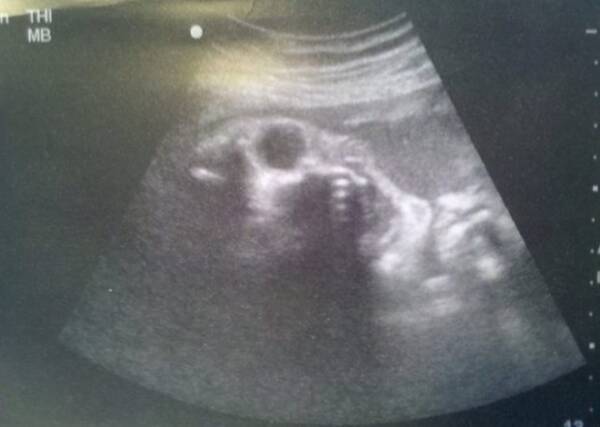

画像ありエコー写真と実際の顔を徹底比較! 4Dエコー撮影 私のエコー写真を見てみると4Dエコーなどのお写真を撮る時は 25週から27週あたりが1番実際のお顔に近い んじゃないかなと思いました(^^) 出産に近付くと見えにくくなりますし、とってもぶちゃいくにうつりますw 2522gでした! · エコーと実際の赤ちゃんはどのぐらい違う?まとめ エコー写真と実物の赤ちゃんを比較すると、エコー写真の方が実物よりパーツが大きめに写っている印象でした。 ですが、大体のフォルムはエコー通りでした。4dエコーが丸わかり!オススメの時期はいつからいつまで?料金 4dエコーを見る最適な時期として、医師によって様々な見解がありますが、 胎児の全体像を見ることのできるのが15~週(4か月後半~6か月前半) ・ 表情がはっきりしてくるのは25~30週頃(7か月中盤~8か月中盤) と言われています。

4Dエコーと実際の顔を生後7日間の徹底比較!画像で検証 4Dエコー(超音波検査)とは?3Dエコーとの違いや料金などまとめ 妊娠32週目(32w0d~6d)のエコー写真とエピソード|妊娠9ヶ月 画像ありエコー写真と実際の顔を徹底比較!!4Dエコー撮影実際、エコー写真と産まれた後の顔は似ているのか? 4dエコー 今妊娠されている方、エコーって一体どれくらいの精度で実際の胎児の姿を映してるんだろうって思いませんか? 私は凄く気になりました。 なので、少し比較写真を乗せたいと思います。 · 今妊娠されている方、エコーって一体どれくらいの精度で実際の胎児の姿を映してるんだろうって思いませんか? 私は凄く気になりました。 なので、少し比較写真を乗せたいと思います。 とはいえ、我が子はエコーで全くお顔を見せてくれませんでした。

スポンサーリンク 息子が生まれる前、検診に行って4dエコーの画像を見ては「パパとママどっちに似てるんかな」とか「イケメンかな」とかいろいろと妄想を膨らませていました。 ちなみにそのときのエコーの写真がこちら。 いやー、すごい技術ですよねー。私のエコー写真を見てみると4Dエコーなどのお写真を撮る時は 25週から27週あたりが1番実際のお顔に近い んじゃないかなと思いました(^^) 出産に近付くと見えにくくなりますし、とってもぶちゃいくにうつりますw ↑実際の顔写真と3Dを比較 エコー写真すごい。0506 · エコー写真あり妊娠初期に出血をするとダウン症!?胎動が少ないとダウン症? 画像ありエコー写真と実際の顔を徹底比較!!4Dエコー撮影おすすめ時期はいつ? 性別ジンクス &baby nubどれが当たるのか検証した結果画